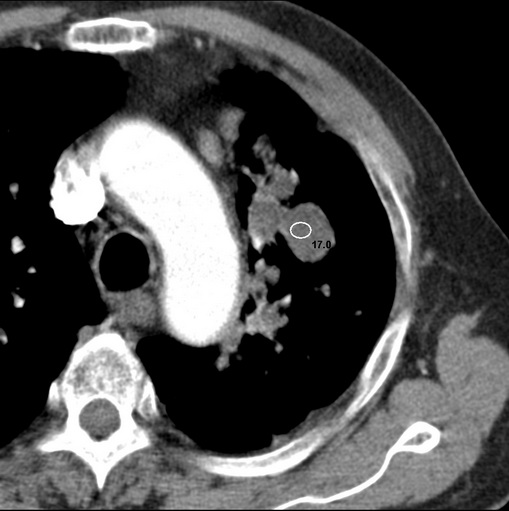

标题: CT25434:胸部CT增强扫描

男性患者 81岁 咳嗽 咳痰 咯血

肿块贴近左肺门,包绕左上肺动脉,形态不规则。肿块增强扫描中度强化。纵膈内主动脉弓左旁间隙、气管隆突前、下间隙见多枚淋巴结影。综上考虑左侧中央型肺癌可能性大。图片没有完整上传,尤其是左肺上叶支气管分支层面没有上传,因此不好判断是叶支气管中断还是段支气管中断。另外,下图红色部分所示是“黏液支气管征”吗?